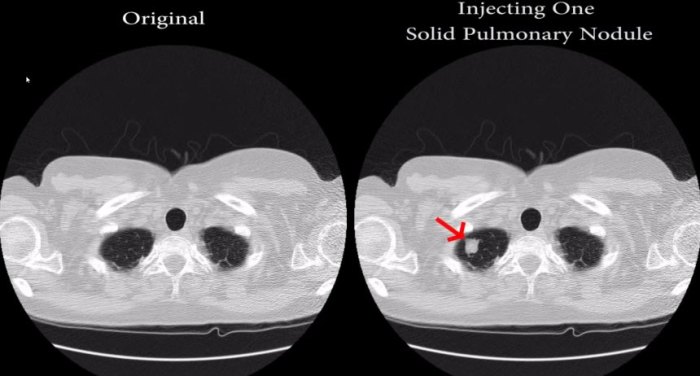

Screenshot aus dem Video der Forscher. Hier wird gezeigt, wie Hinweise auf eine Krebserkrankung in eine Bild hineinmontiert werden.

In einer simulierten Cyberattacke auf ein Krankenhaus zeigten die Forscher, wie ein Angreifer mithilfe spezieller Malware die fraglichen Bilddateien verändern könnte. Dabei wäre es mit ihrer Technik sowohl möglich, eine Krebserkrankung vorzutäuschen, als auch einen vorhandenen Befall mit Krebszellen von den Bildern verschwinden lassen kann.

Um zu untermauern, wie glaubhaft ihre Software die medizinischen Diagnosebilder manipuliert, legten die Forscher solche Bilder drei Fachärzten vor und liessen sie von einer Radiologiesoftware analysieren. Dabei stellten die Fachleute in 99 Prozent der Bilder, die einen Krebsbefall vortäuschen sollten, eine Krebsdiagnose. Bei der Software, die vielen Ärzten als Grundlage für ihre Diagnose dient, lag die Erfolgsquote gar bei 100 Prozent. (Netzwelt, Spiegel)